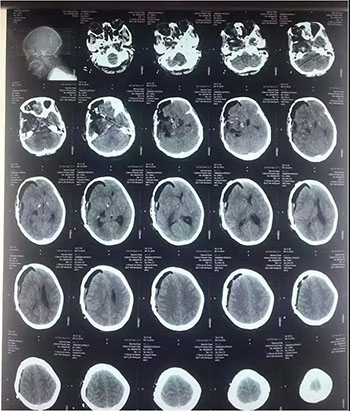

中脑海绵状血管瘤手术

术前